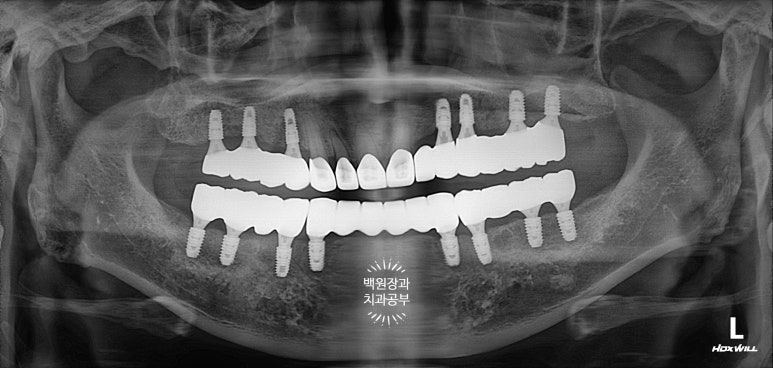

마지막 치과용 파노라마도 촬영해보아야겠죠?

가장 중요한 것은 아주 적절한 위치에 적절한 방향으로 임플란트가 위치하고 있다는 점입니다.

이것이 네비게이션 임플란트의 가장 큰 장점이라고 할 수 있습니다!!!

의료진의 경험을 컴퓨터 기술의 정밀함이 보완함으로써 최상의 결과를 가져오는 치료입니다.

임플란트를 3개 이상 수술 받으셔야 한다면.. 네비게이션 임플란트를 권해드립니다. 그리고 꼭 경험 많으신 치과의사 선생님을 찾아가세요.